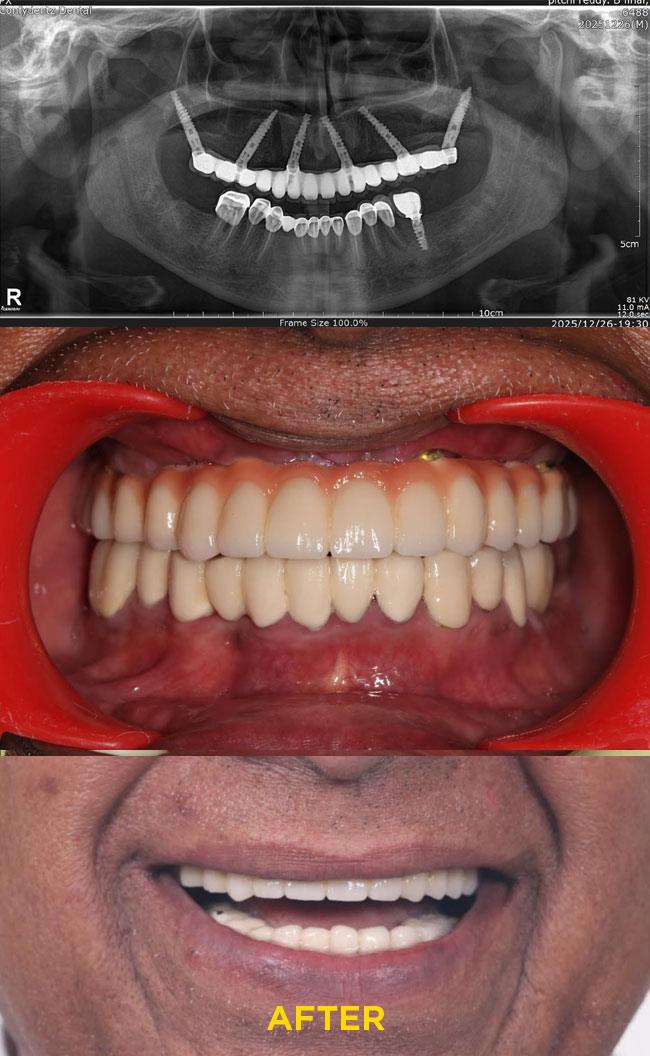

Case - 2